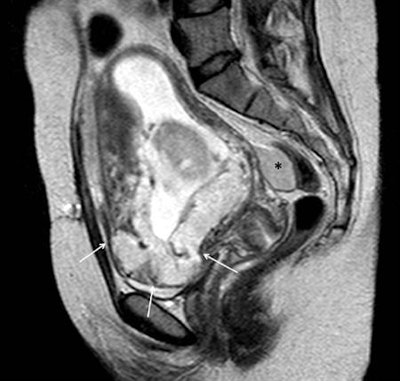

Placenta previa refers to abnormal implantation of the placenta in the lower uterine segment, overlying or near the internal cervical os, they continued. It can be further subdivided according to its position relative to the internal cervical os in low-lying, marginal, complete previa, and central previa placenta.

Previous uterine surgery predisposes to abnormal adherence or penetration of the chorionic villi to or into the uterine wall, the extent of which further subdivides the "abnormal" placenta to placenta accreta (superficial invasion of the basalis layer), placenta increta (deeper invasion of the myometrium), and placenta percreta (even deeper invasion of the serosa or adjacent pelvic organs), which may lead to thanatophoric hemorrhage at the time of the placental delivery, often necessitating emergent hysterectomy, the researchers stated.